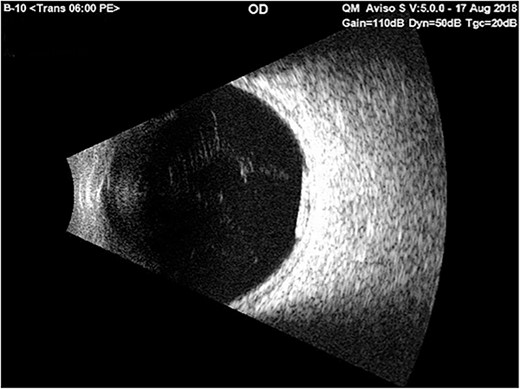

Just before the planned implant removal surgery, the examination indicated no Ozurdex implant in the anterior chamber; the surgery was postponed for re-evaluation. B-scan ultrasonography revealed the Ozurdex implant was back in the vitreous and showed a highly reflective small tube inferior and posterior to the equator and freely mobile (Fig. 3). The patient was discharged with hypertonic saline and topical prednisolone for corneal edema. On follow-up 2 weeks later, the fundus examination showed that the implant was still in place at the vitreous.

Ultrasound b-scan exam of the right eye showed a reflective small tube inferior and posterior to the equator on the 1st day of admission with only bed rest in the supine position and using cycloplegic drops.